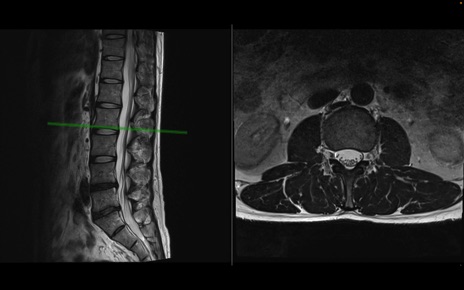

【整形】TIPS症例1 腰椎MRI 横断像と矢状断像

【症例】40歳代男性

【主訴】左臀部〜大腿後面痛み

【現病歴】2週間前から腰痛あり。2日前に夜中にくしゃみをした際に激痛が出現。疼痛強いため来院。

【身体所見】左臀部〜大腿後面、下腿後面のしびれ。SLR -/+ 30度、うつ伏せ困難、筋力低下なし。

異常所見と診断は?